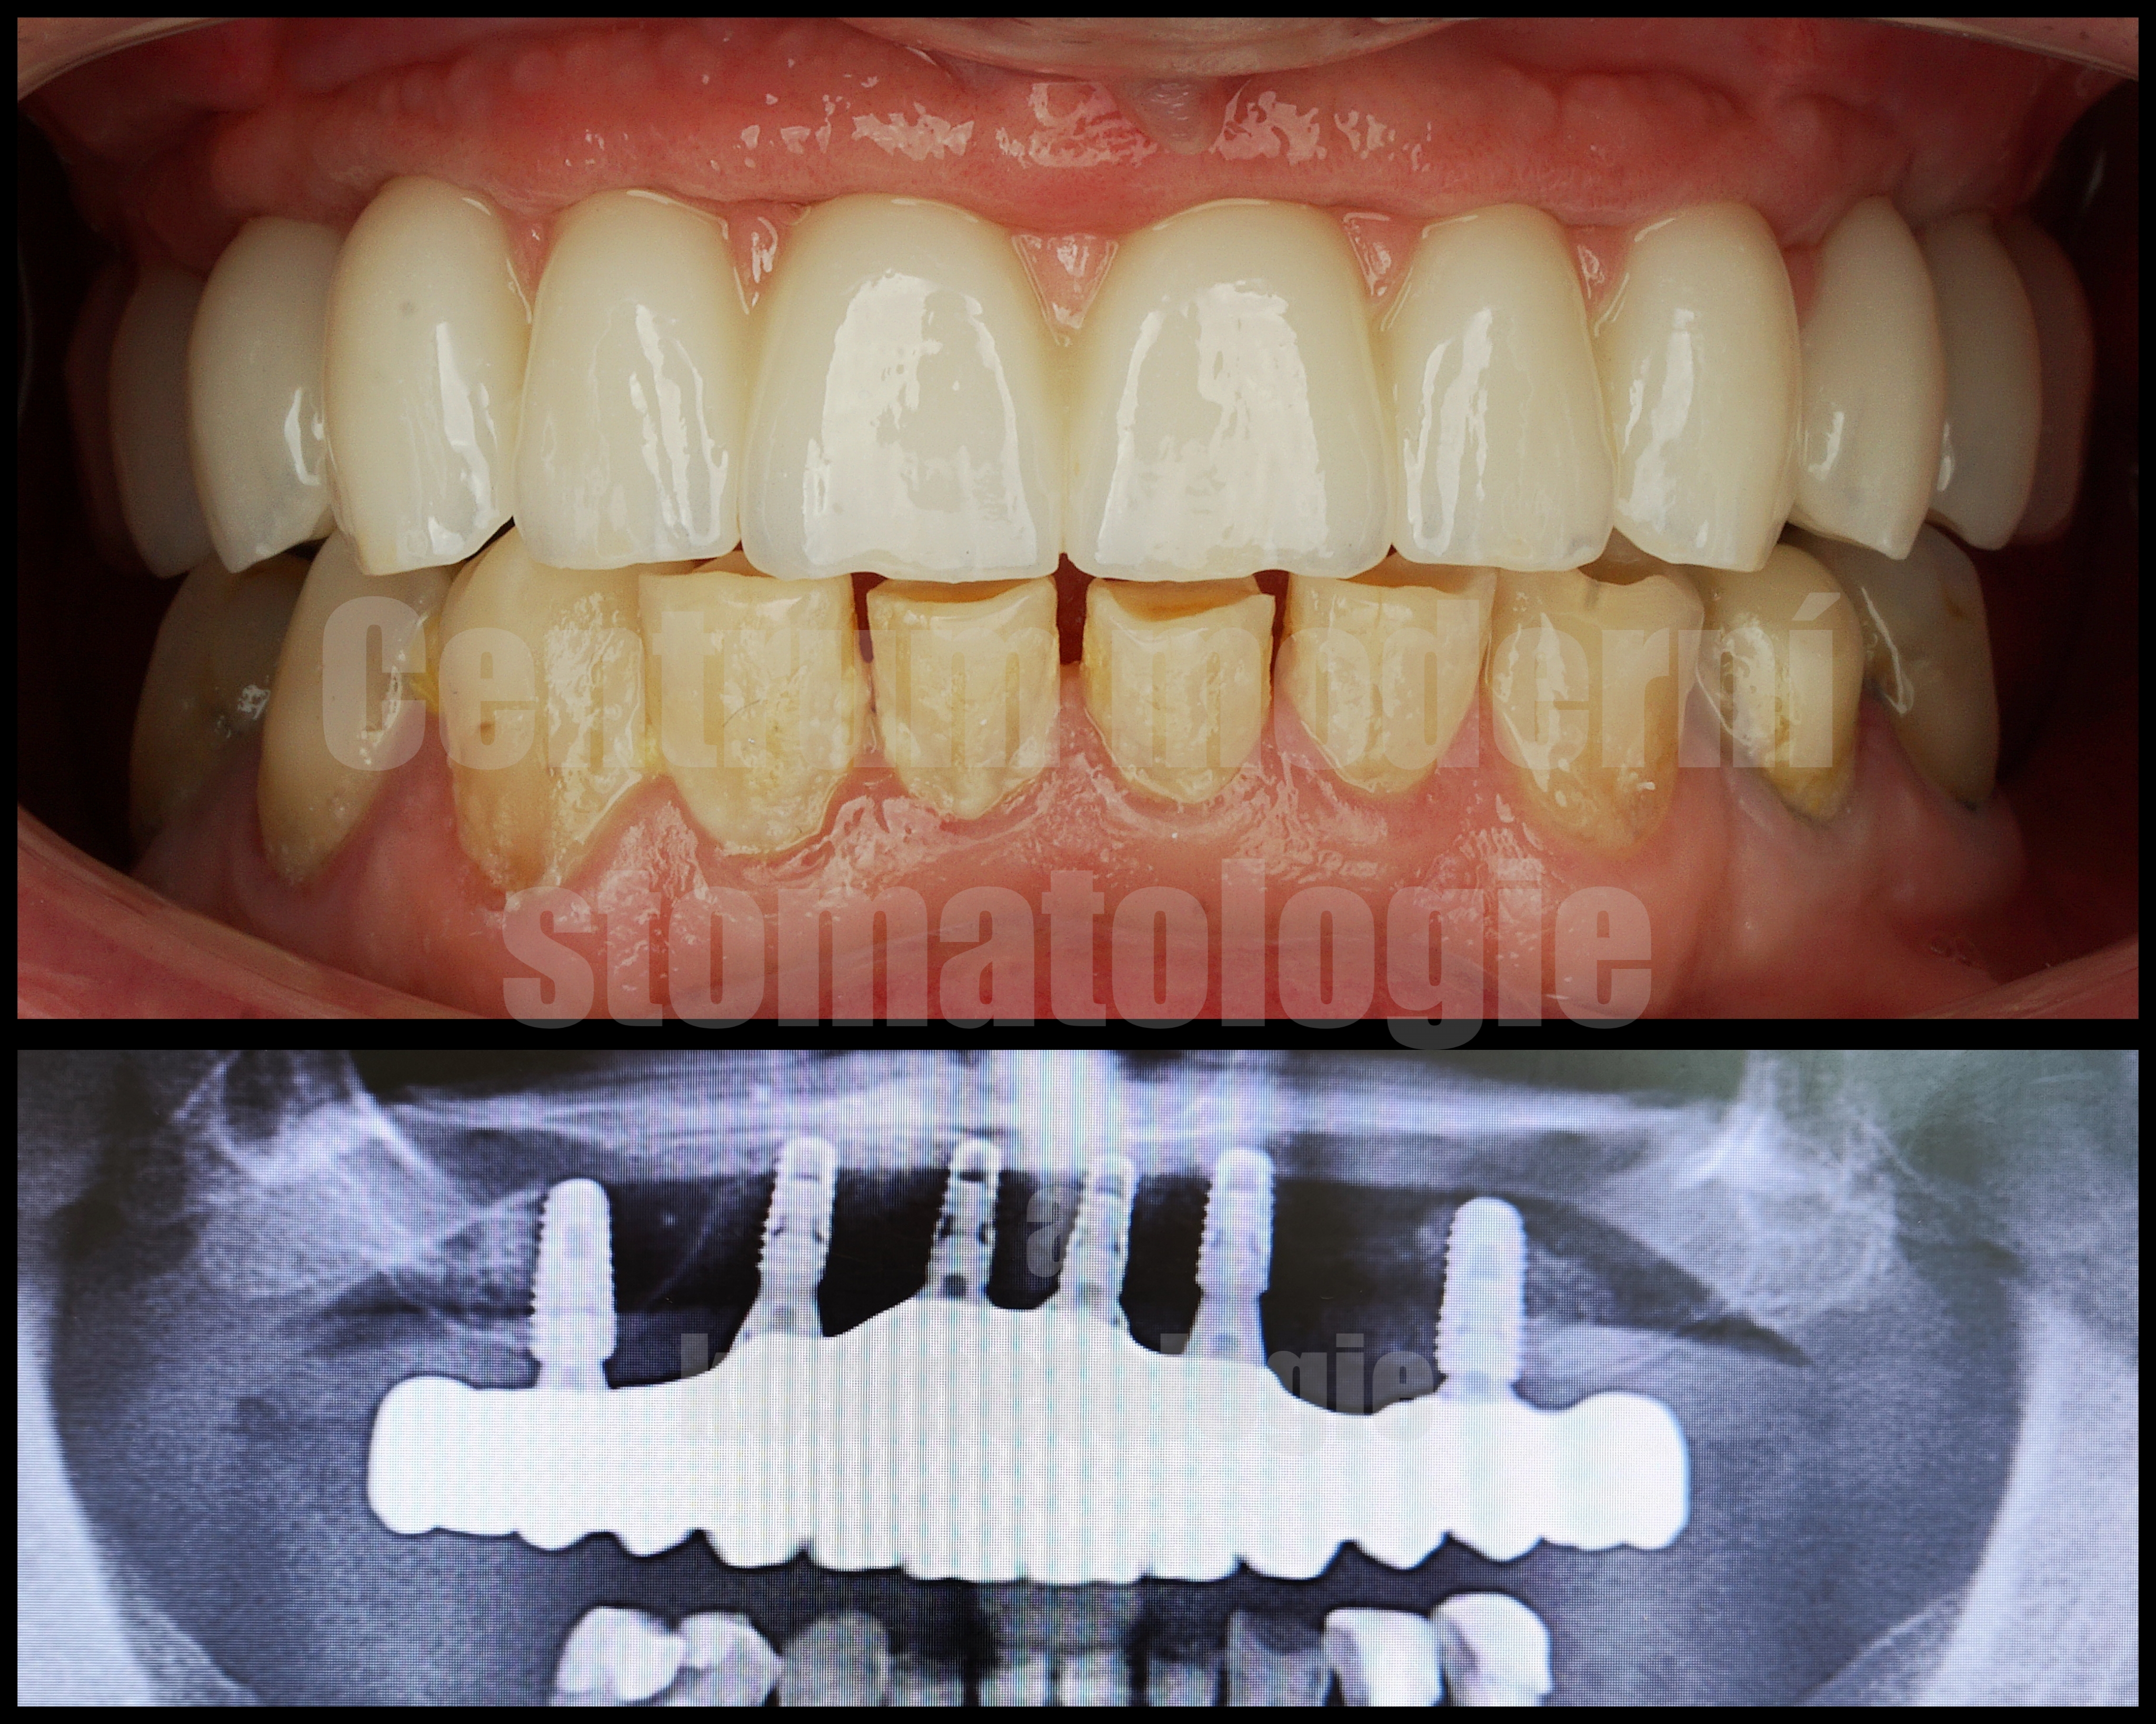

All-on-6 je moderní způsob náhrady celého zubního oblouku pomocí šesti implantátů, na kterých je upevněna fixní protetická práce.

Cílem ošetření All-on-6 je obnovit estetiku úsměvu, jistotu při kousání a komfort při každodenním fungování. Vhodnost tohoto postupu závisí na anatomii čelisti, kvalitě kosti, skusu a celkovém léčebném plánu.

Léčba All-on-6 začíná vstupní konzultací, při které zhodnotíme stav chrupu, dásní a kostní tkáně. Součástí plánování je klinické vyšetření a zobrazovací diagnostika.

Pokud jsou přítomny zuby, které již nelze dlouhodobě zachovat, může být součástí léčby jejich odstranění. Následně je podle léčebného plánu zavedeno šest implantátů, které slouží jako opora budoucí fixní náhrady.

Po implantaci následuje hojení. Za vhodných podmínek je v některých případech možné provést dočasné zatížení protetickou náhradou v krátkém čase po zákroku. Definitivní práce se zhotovuje po stabilizaci a vhojení implantátů.